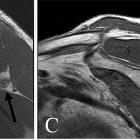

fatty infiltration of the teres minor in patients with shoulder pain? A review of 7,367 consecutive MRI scans. Sagittal T1-weighted MRI demonstrating fatty infiltration of the teres minor muscle in 4 patients